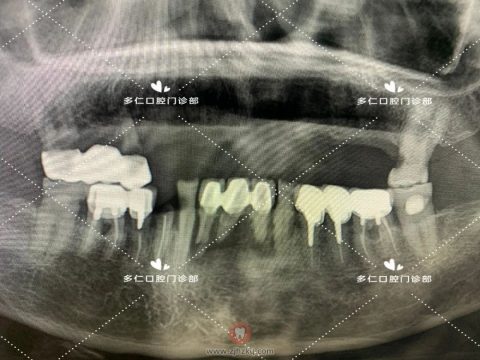

术前CBCT